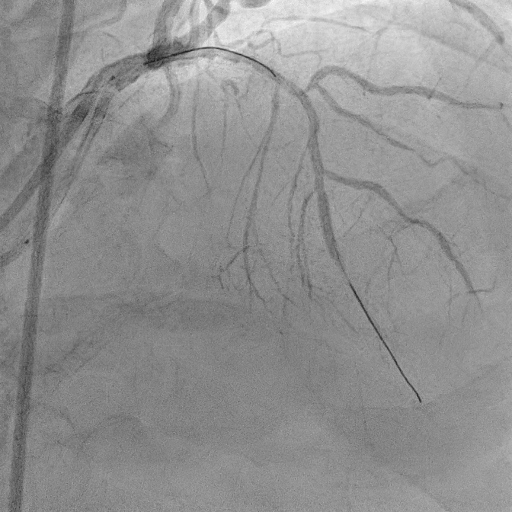

The procedure commenced with EBU 3.5/6F catheter and CTO wire with microcatheter. Managed to cross the lesion and changed to workhorse wire. Proximal LAD ISR predilated with SC balloon 2.0/15mm. CTO at mid segment predilated with same balloon. However, noted perforation at mid LAD after predilatation. We used the same balloon to tamponade the perforation and attempted to wire down distal LAD with another wire but failed. Right femoral puncture was performed and another EBU3.5/6F was used. The ping pong technique was used in which another workhorse wire to distal LAD when tamponade balloon was deflated. However, the covered stent was unable to cross the proximal LAD. Proximal segment was then predilated with NC 2.5/15mm, yet still unable to advance the covered stent. Subsequently, guide extension GuidePlus II was used and managed to advance covered stent 2.5/20mm. Tamponade balloon was then removed and covered stent deployed at perforation site. We proceeded with drug coated balloon angioplasty to proximal-mid LAD using DCB 3.5/20mm. Patient was stable and bedside echo revealed minimal pericardial effusion only

Coronary artery perforation is rare but potentially lethal complication. Early recognition and immediate balloon occlusion are crucial in preventing cardiac tamponade and haemodynamic compromise. Double catheter guide technique (ping pong) allowed controlled delivery of covered stents to perforation site. It ensures uninterrupted balloon occlusion of perforated site and smooth delivery of bulky covered stents.